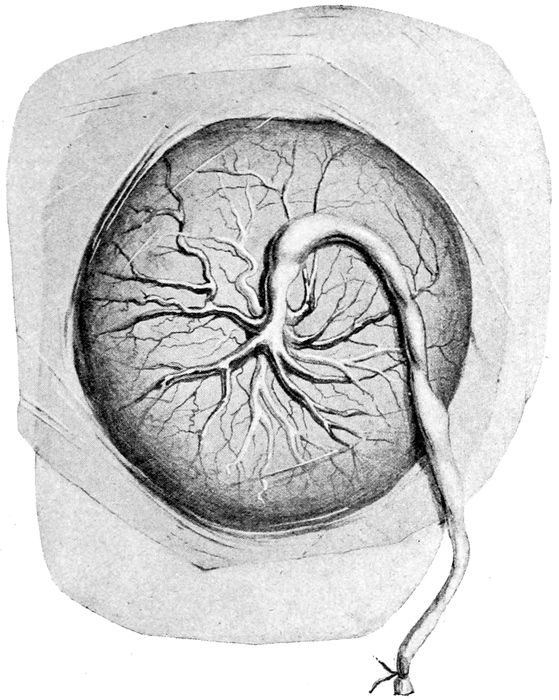

Fœtal surface of human placenta |

Fig. 18.—Fœtal surface of human placenta. (Eden.)